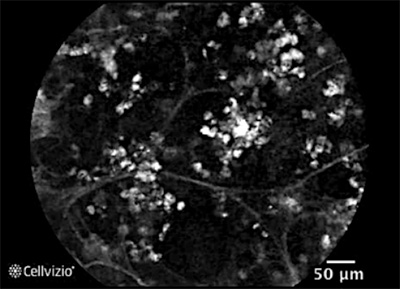

La microscopie confocale est une sorte de microscope qui permet de voir les cellules et l’architecture du poumon au cours d’une endoscopie et de façon totalement indolore. Elle a été obtenue par des fonds de recherche de l’INSERM et représente un outil très précieux de recherche.

La photo 2 vous montre la machine et la photo 3 une image obtenue.

Vous voyez par exemple ici le poumon d’un patient greffé pulmonaire : On retrouve le maillage régulier comme dans une ruche des alvéoles pulmonaires avec des cloisons très fines. Les cellules à l’intérieur (en blanc) qui font 10 à 15 microns sont des macrophages.